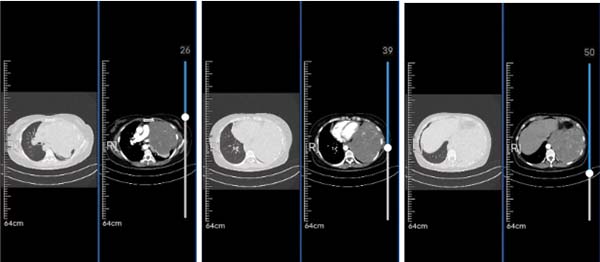

术前医学影像

50岁的赵女士(化名)平时工作繁忙,疏于健康管理,长时间未进行体检。一个月前因劳累后出现胸憋、气紧情况就医,胸部CT检查显示:左胸腔巨大肿瘤、左侧胸腔积液。因手术风险极高,患者为能得到更加专业的诊疗,辗转多家医院后选择在我院胸外科进行系统治疗。

胸外科副主任胡成广接诊该患者,仔细阅读其影像、病历资料,资料显示,患者肿瘤十分巨大,完整切除手术难度极高。赵女士的胸腔,被巨型肿瘤侵占了大部分空间,难以保证良好的手术视野,且肿瘤与心脏及血管关系密切,一旦术中损伤,很可能导致不可逆转的大出血。由于肿瘤侵袭的范围太广,如不能找到确切的解剖层面,会直接导致切除不彻底或无法切除。肿瘤几乎占据了整个左侧胸腔,压迫导致长时间肺不张,术中可能发生复张性肺水肿或诱发呼吸衰竭等严重并发症。考虑患者病情十分复杂,手术难度和风险较高,胸外科立即组织团队诊疗,在严谨的讨论和多番交流后,制定出缜密的手术方案,同时决定“强强联手”。